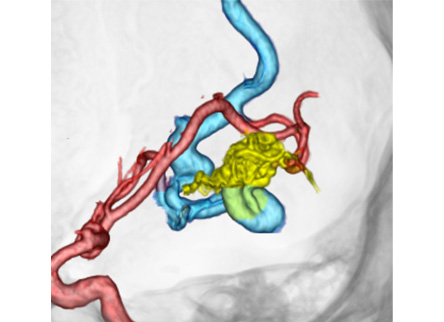

脳動静脈奇形は脳実質内に発生し、本来あるはずの動脈と静脈を繋ぐ毛細血管がないために動脈の血流がそのまま静脈へ流れてしまい、その動脈と静脈の吻合部に異常血管の集合体(ナイダス)を形成する病気です。

治療は出血を予防するために行います。摘出術や血管内治療による塞栓術、放射線治療(ガンマナイフ)を適宜組み合わせて治療を行います。

②血管内治療(塞栓術)

一般的に塞栓術のみでは根治は困難であり、あくまで支援的な手段と考えられています。

塞栓術による完全閉塞率は6~40%、1年内の再開通率は12%と報告されています。

塞栓術を行うことで、ナイダスの大きさを縮小させ、摘出術の際に周囲の組織から剥離を容易にし、出血を少なくでき、手術時間の短縮や安全性向上につながります。